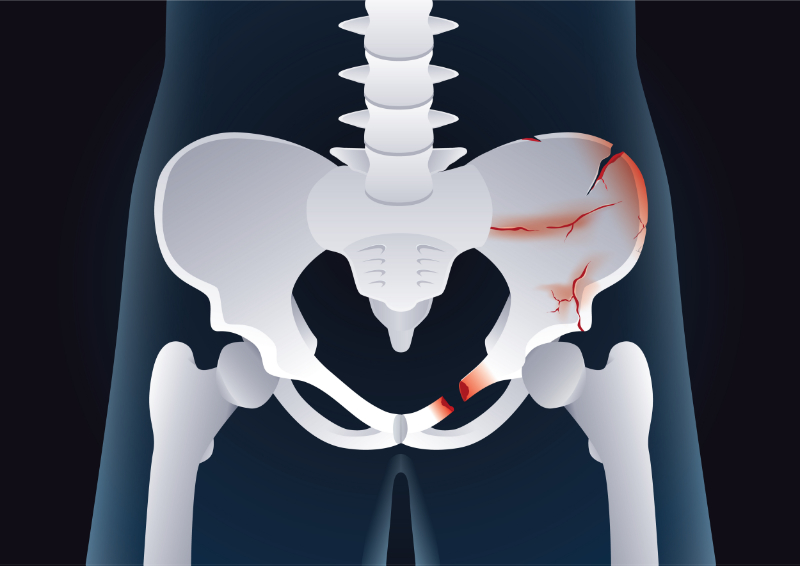

Inspect and palpate the pelvis. Ecchymosis over the pelvis or tenderness along with the pelvic ring warrants diagnostic imaging. Examination findings (e.g., instability) or imaging studies consistent with pelvic ring disruption indicate the need for pelvic immobilization and immediate orthopedic evaluation (Image 5). Repeat examinations to assess pelvic stability are unnecessary and likely to exacerbate bleeding

Image 5: Pelvic Fractures

Image Source: Licensed from Shutterstock

The unstable pelvis should not be manipulated multiple times since additional manipulation exacerbates hemorrhage. Once suspected, open or unstable pelvic fractures should be stabilized using a pelvic binder or a sheet if no binder is available. If the patient is hemodynamically stable, CT imaging is obtained. The unstable patient requires either surgery or angiography.